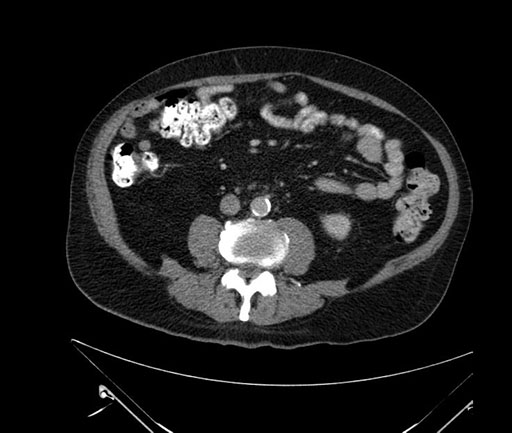

Axial - stented